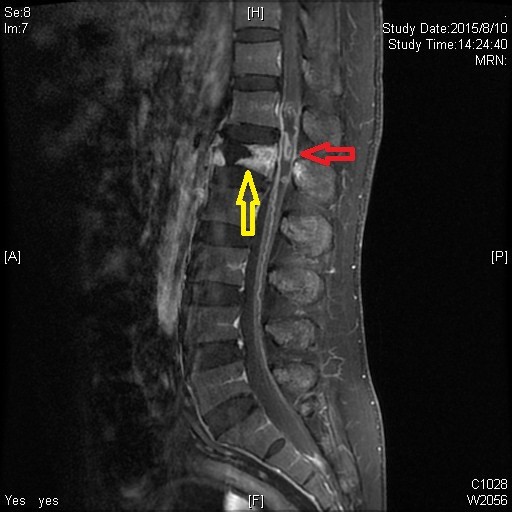

术前MRI:腰1椎体爆裂骨折(黄色箭头),脊髓内出血(红色箭头)。